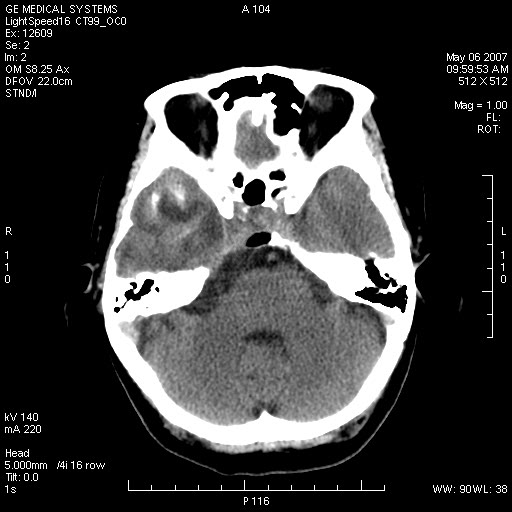

女,60岁,头痛6~7天。

右颞叶巨大高低混杂密度肿块,病灶内可见多发条块状钙化影,占位效应明显,中线结构显著左偏,肿块周围水肿明显,临近颅骨吸收变薄,边缘光整,考虑1少枝胶质瘤2脑膜瘤3转移瘤4室管膜瘤5淋巴瘤6三叉神经瘤(多多益善)合并镰下疝

右颞叶分叶状稍高密度灶,占位效应明显,外周见水肿带,其内见点条样高密度钙化灶,临近颅骨变薄,考虑:脑膜瘤,少突胶质瘤。

右颞叶混杂密度,累及右额叶。其内可见条片状钙化及斑片状略高密度,周围少量水肿,右颞骨吸收变薄,中线结构左移。考虑1少突胶质瘤。2脑膜瘤。合并瘤卒中。建议增强扫描。

右额、颞叶巨大高低混杂密度肿块,病灶内可见多发条块状钙化影,占位效应明显,中线结构显著左偏,肿块周围水肿明显,临近颅骨吸收变薄,边缘光整。

考虑:1、少枝胶质瘤;

2、脑膜瘤?

3、镰下疝;

4、建议增强扫描进一步检查。